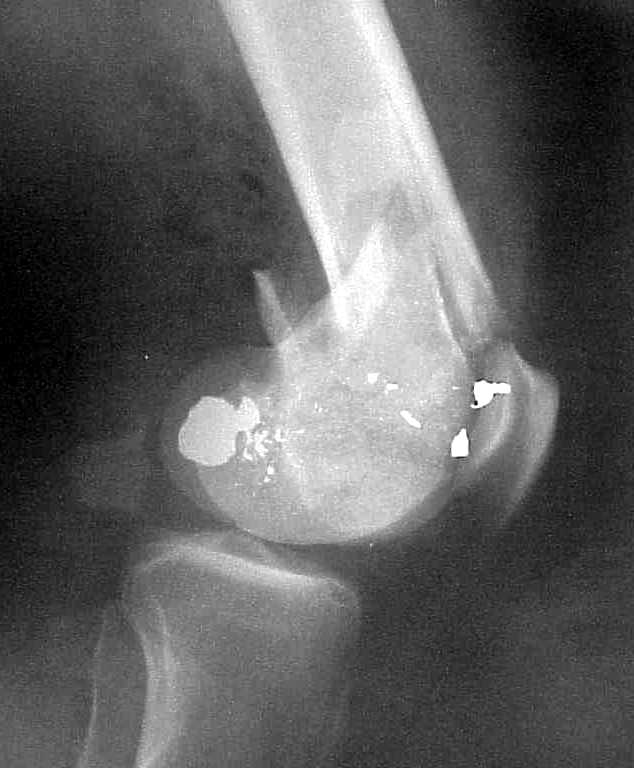

of course the only radiograms both the view of the femur (AP and LL) are not enough in order to assess the condilar ones.

So I think a TAC of the knee could be useful.

I am sure that you assessed adequately the condylar fractures, they may need fixation (eg. percutaneous screws).

A CT and knee xrays would help identify lateral condyle comminution and/or a "hoffa fragment" of the posterior condyle. I am concerned that the lateral cortex is not sufficient to give purchase for a retrograde IMN. blocking screws could improve this as a possibility. A long blade or LISS if avaible would be my secondary choices. Good luck. Any chance you can get these cases transferred earlier when it